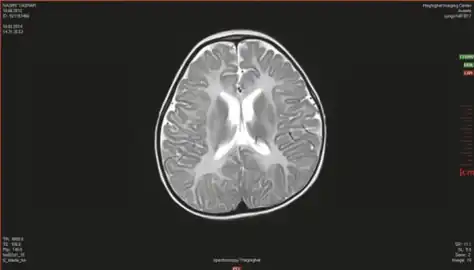

MRS in individual with Canavan disease shows a markedly increased level of N-acetylaspartic acid

Canavan’s disease demonstrates bilateral symmetric T2 white matter hyperintensity including involvement of the subcortical arcuate fibers